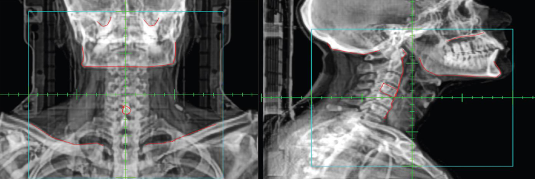

identify a Digitally Reconstructed Image (DRR)

What type of image is this?

KV/KV